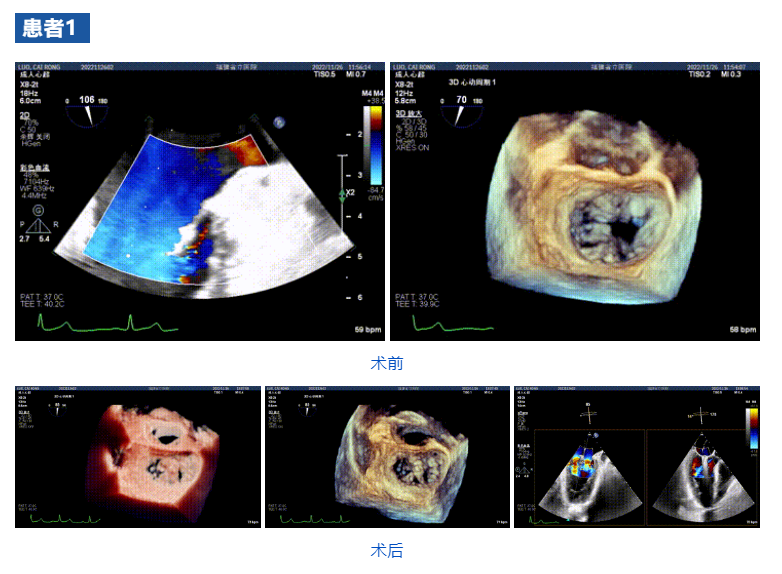

接受治療的三例患者均為器質性重度二尖瓣反流(DMR)患者,術前超聲提示二尖瓣后葉脫垂伴4+反流,左室舒張功能減退。郭延松教授攜同團隊成員陳新敬副教授和洪景宣、方明程、楊清勇主治醫師、心外科丁杭主任以及超聲科賴寶春、葉振盛主治醫師共同進行病情討論。考慮到患者高齡、基礎疾病多、STS評分高,為外科手術極高危患者,不適合進行外科開胸二尖瓣手術,因此決定為患者實施經導管緣對緣修復介入術(JensClip經導管瓣膜夾系統)。

在浙江大學醫學院附屬第二醫院王建安教授團隊的支持下,手術經股靜脈-房間隔入路,采用全身麻醉插管,在TEE和DSA引導下完成房間隔穿刺。置入JensClip瓣膜夾系統后,在左房調整瓣膜夾的位置和軸向,后進入左室,在TEE引導下捕捉二尖瓣前后瓣葉,并關閉瓣膜夾。經TEE反復確認手術效果后最終鎖定并釋放瓣膜夾。術后即刻超聲顯示瓣膜夾位置穩定,功能良好,二尖瓣反流由術前4+減少至微量,手術圓滿成功。